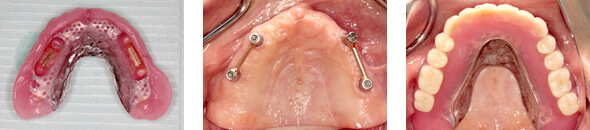

インプラント義歯とは?

インプラント義歯

あごの骨にインプラント(ネジのようなものを埋め込んだもの)をうえて、そのインプラントを土台として入れ歯を装着する方法です。インプラントを片あごに4本埋入して、アタッチメントを取り付けます。

入れ歯をしっかりと固定することができ、入れ歯のがたつきにより発生する痛みもありません。(インプラントの必要本数が確保できない場合や、治療時間・金銭面の負担を軽減させたい時)

義歯もインプラントの時代です

歯科のインプラントの普及により、インプラントを利用したオーバーデンチャーも増えています。

顎堤の吸収の大きなケースや、もっと安定して噛みたいと言う願望を叶えるための1つの重要な方法です。少ないインプラントの数で大きな効果を発揮できます。